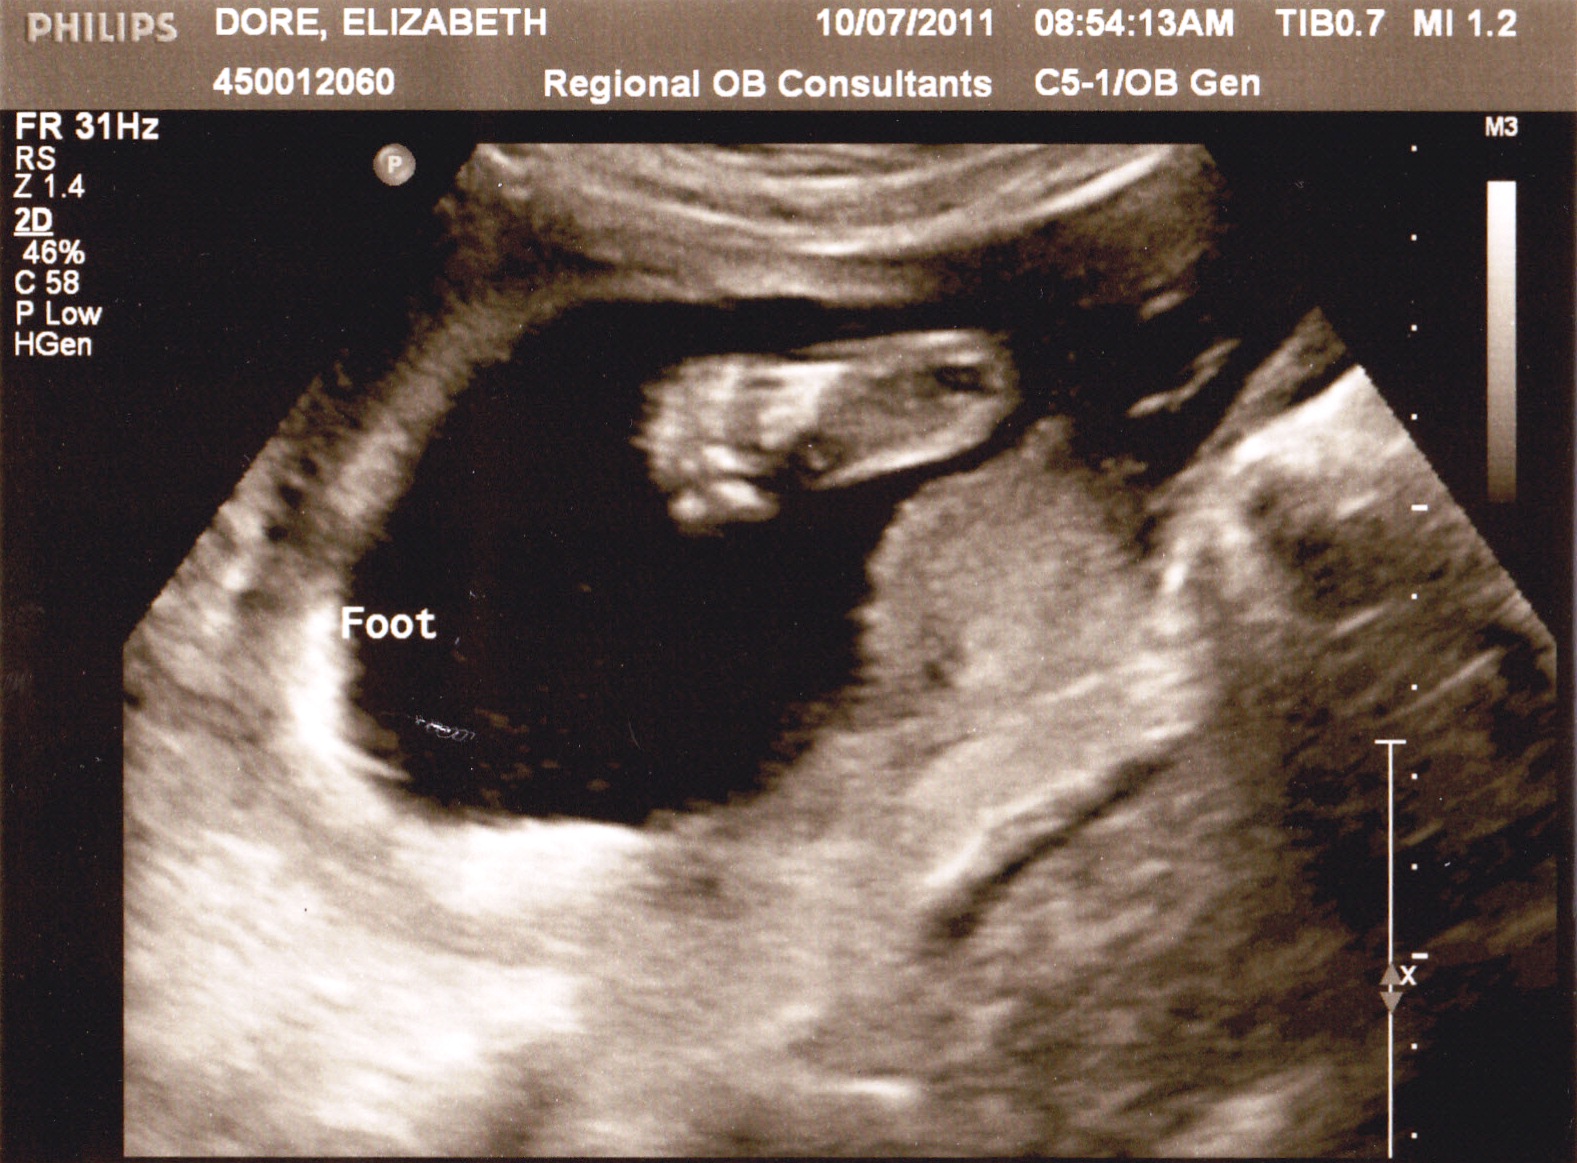

23 week ultrasound- profile view

A chubby little foot :-)